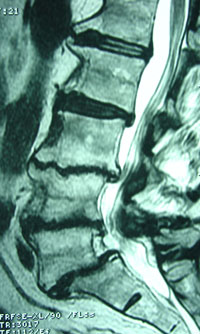

Well, at Aurora Chiropractic Center, we understand that the discs in your spine are 80% water when they are young and healthy. As you get older and with damage, the discs lose water and that progresses to the condition called disc degeneration.

To stress this aspect, a study chronicles that lower back pain disturbs up to 85% of all persons at some time in life. Additionally, lower back pain is a predicament for which spinal manipulation has been shown to be beneficial. Researchers study actions that can recuperate the efficiency of spinal manipulation. One such step, hydration status, was investigated: The spinal discs of 8 women and 11 men with lower back pain of 1 to 12 months’ length were normal or underhydrated and then hypohydrated for 36 hours before having spinal manipulation. (1) All they did was increase water intake for the 36 hours prior to their spinal manipulation sessions (which we know our Juneau chiropractic patients could easily do!).